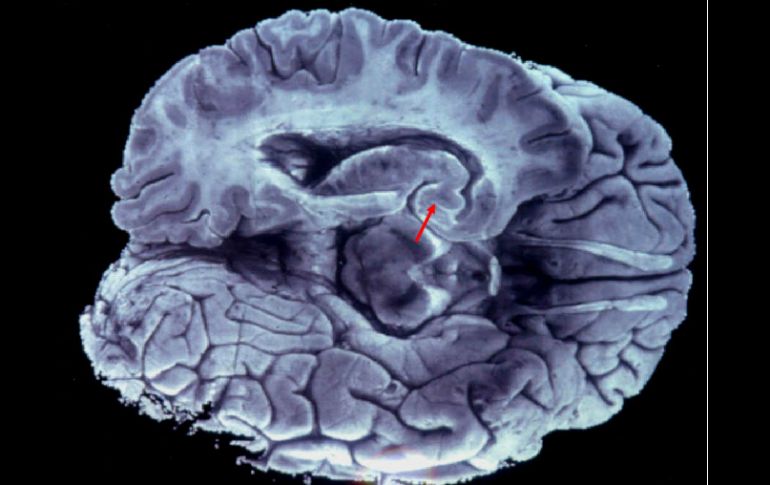

Al confiarle todo a la tecnología, estamos dejando espacios en nuestro cerebro que podrían utilizarse en actividades intelectuales. ARCHIVO /

Al confiarle todo a la tecnología, comentó, estamos dejando espacios libres en nuestro cerebro que bien podrían utilizarse en actividades intelectuales, pero en la mayoría de los casos no es así.